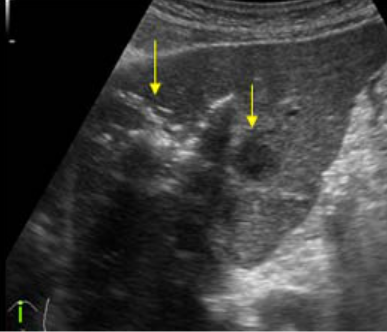

polycystic liver disease ③ bile duct hamartomas

다발성 담관 하마토마 또는 Von Meyenburg 복합체라고도 알려져 있다. 배아 발생기간 동안 얽히지 않은 발생학적 잔해인 확장된 낭포성 담관을 특징으로 하는 희귀한 양성 간 기형이다. 일반적으로 크기가 작고 (5mm 미만) 간 전체에 흩어져 있는 여러 병변으로 나타난다. 대체로 증상이 없으며 비교적 양성 질환 경과를 보인다. 하지만 악성변형과 관련이 있을 수 있으므로 의심스럽거나 진행 중인 병변은 확실한 진단을 위해 추가로 정밀검사를 통한 확인이 필요하다.

US finding

- comet-tail artifact

- 크기가 작고 간전체에 흩어져 보임(multiple small hyperechoic lesion)

- echos scattered through the liver ( <1cm )

bile duct hamartomas ④ caroli disease